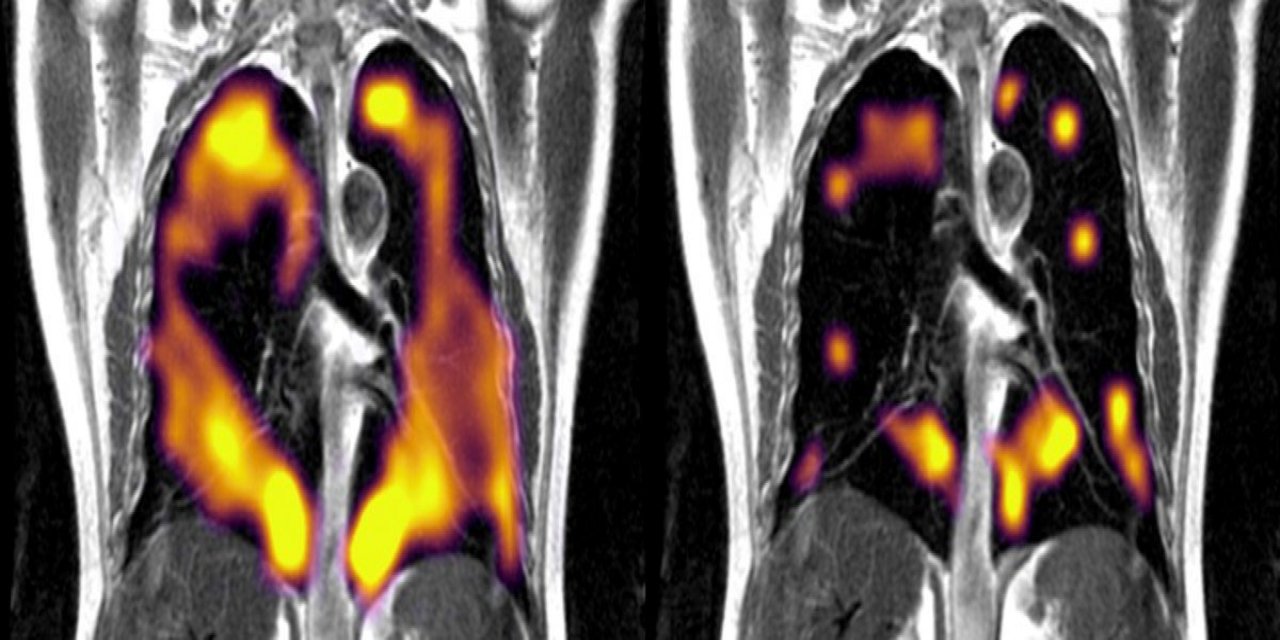

Covid-19’u hafif geçirenlerin akciğerlerindeki gizli hasar ortaya çıktı